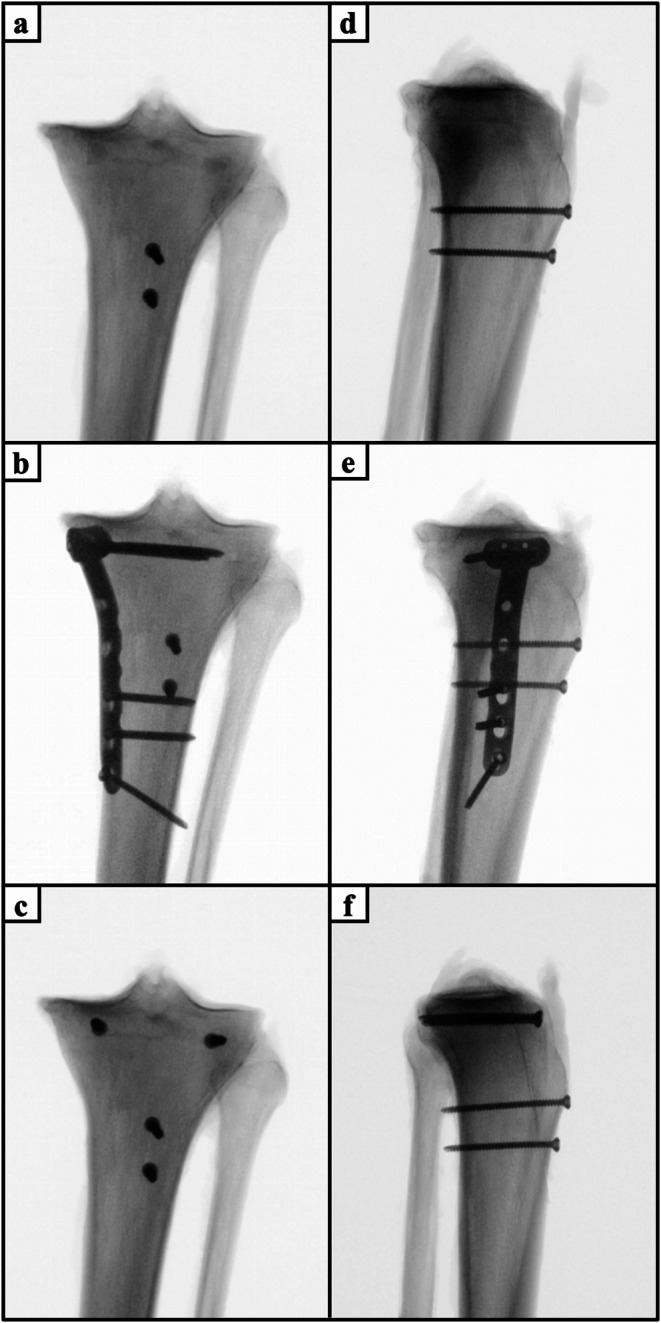

Methods: Two different types of apoepiphyseal tibial tubercle avulsion fractures were created in 40 proximal tibiae according to the modified Ogden classification: (1) Ogden type IIIA and (2) Ogden type IV. The fractures were fixed with either isolated apophyseal screws or additionally with a medial plate or epiphyseal screws. All specimens were biomechanically tested under progressively increasing cyclic loading until failure, while capturing the interfragmentary movements with motion tracking.

Results: Augmentation of apophyseal screw osteosynthesis by a medial plate in Ogden IV fractures or epiphyseal screws in Ogden IIIA fractures exhibited significantly higher cycles to failure and failure loads (P< 0.05), and significantly less axial displacement (P < 0.05) compared to isolated apophyseal screw fixation. Fixation of Ogden type IIIA fractures resulted in significantly less axial displacements and higher construct stiffness, cycles to failure and failure loads compared to Ogden type IV fracture (P < 0.001). Fracture gap opening did not differ significantly between the fixation techniques.